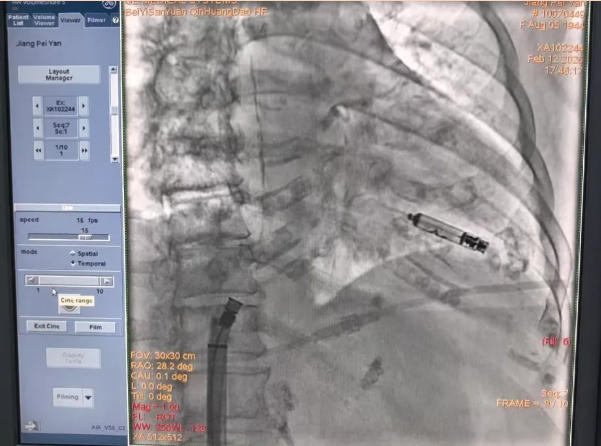

最终,在麻醉科团队严密且精准的监护之下,谭院长与王主任带领的手术团队配合默契、操作精准无误,成功完成了这例极具挑战性的无导线心脏起搏器植入术。当手术结束的那一刻,生命的奇迹如约降临:患者的心率瞬间回升至安全区间,原本存在的胸闷、气短症状完全消失不见,心衰的关键指标NT-proBNP从术前的 11901pg/ml大幅度下降至447.2pg/ml,心功能、肾功能等衰竭脏器的功能均得到了显著改善。更为惊喜的是,由于供血状况得到改善,老人原本因阿尔茨海默病导致的痴呆状态也有了明显好转,意识逐渐变得清晰。术后仅3天,老人就顺利出院,回到了家中,重新收获了健康。